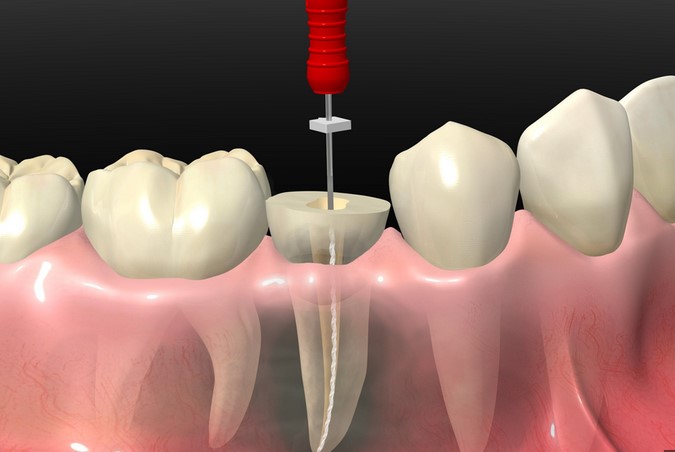

Conducto

El tratamiento de conducto es necesario cuando la pulpa del diente se inflama o infecta. Este procedimiento ayuda a salvar el diente y prevenir la extracción, eliminando la infección y sellando el espacio.